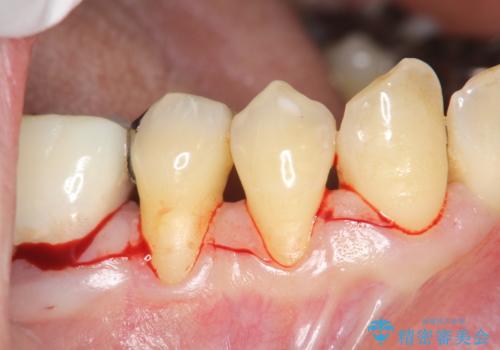

- 右下4番と5番に丈夫な歯肉が不足しているために、徐々に歯肉が下がってきていたケースです。

これ以上の歯肉退縮を防ぐべく、丈夫な歯肉の獲得を目的として結合組織移植術による対応を行いました。

患部にはごくわずかに丈夫な歯肉(角化歯肉)がある状態でした。この丈夫な歯肉の幅を十分に増大させ、厚みを持たせる事で、ブラッシングによっても下がりにくく安定した状態となります。

術式は歯冠側移動術と歯肉結合組織移植術を併用しました。